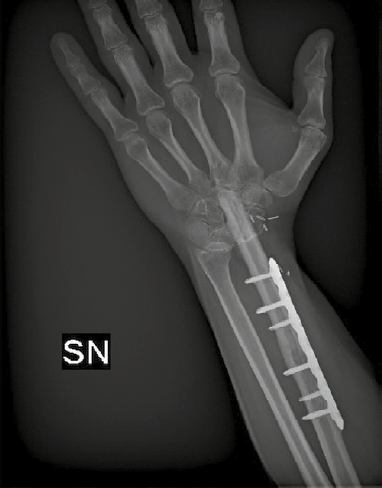

Overall, the choice between arthrodesis and joint-preserving procedures should be individualized, balancing oncologic safety with functional expectations. Factors such as tumor grade, local bone involvement, patient age, occupational demands, and long-term priorities play a decisive role in guiding reconstruction strategy 6,9,14. This tailored approach ensures that surgical management not only secures tumor control, but also provides the most functional and durable outcome for each patient. In Figures 1-3 we present an example case of 28-year-old man with a distal radius GCT resected after denosumab medical treatment and reconstructed with an arthrodesis with microsurgical free fibula (Tab. IV, Figs. 1-3).

Figure 3.Resection and reconstruction with an arthrodesis with microsurgical free fibula (L view).